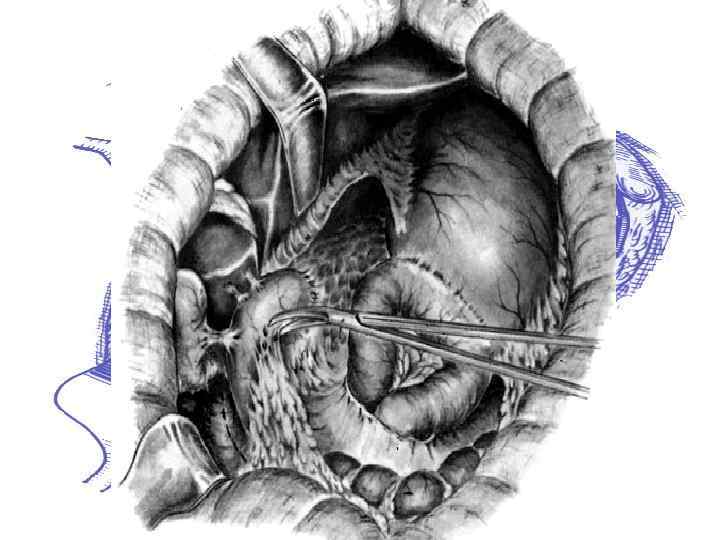

Виды оперативных вмешательств при синдроме приводящей петли: • Реконструкция по Ру-Опокину • Перевод резекции желудка из Бильрот-II в • • Бильрот-I Энтеро-энтероанастомоз по Брауну; Подшивание приводящей петли к малой кривизне желудка;

Варианты оперативного лечения синдрома порочного круга гастроэнтероанастомоза